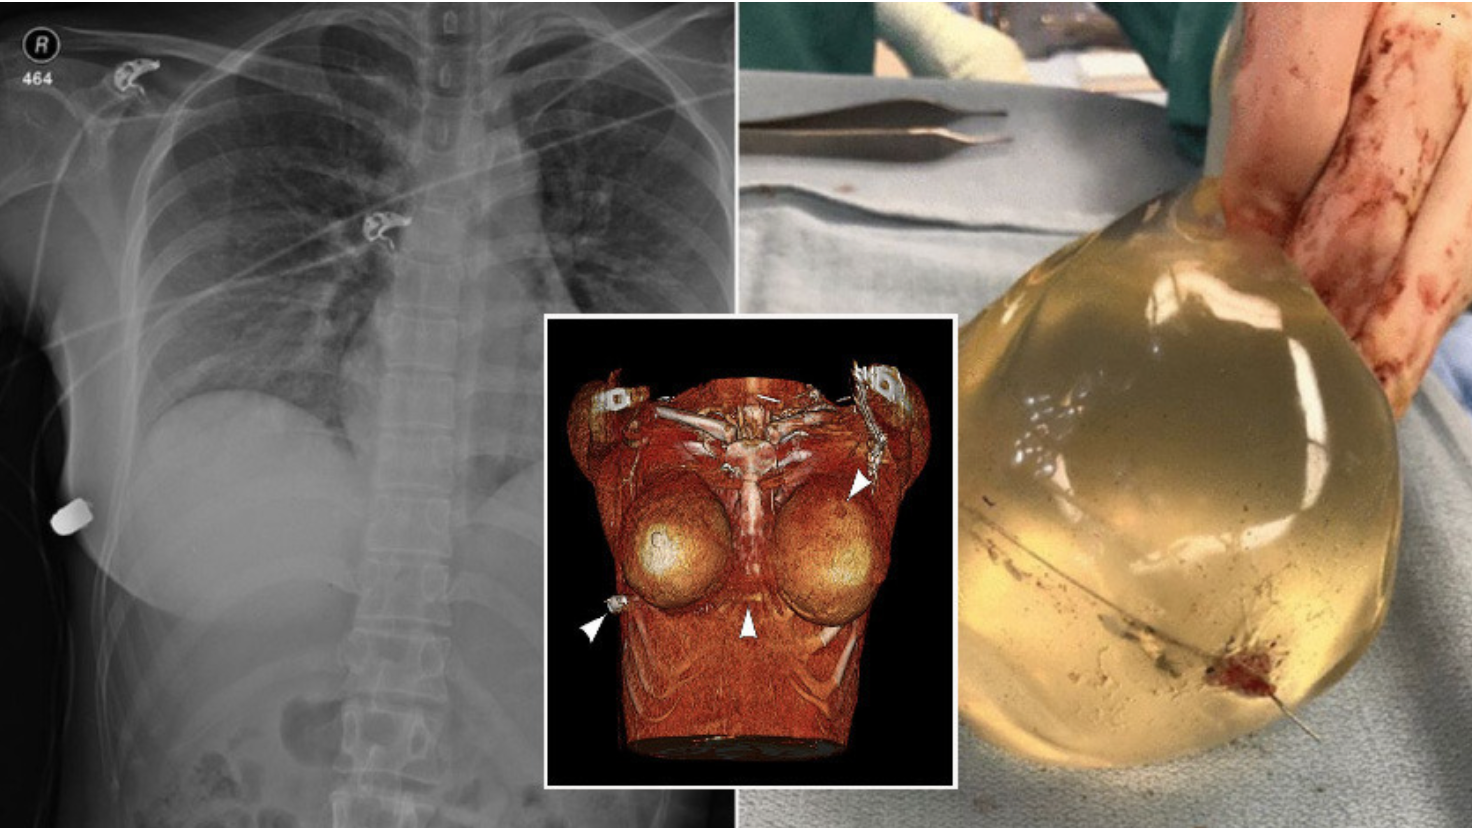

의료진은 A씨가 총상을 입은 것을 확인한 후 수술에 들어갔다가 놀라운 사실을 발견했는데, 그녀의 목숨을 살린 것은 가슴 안에 시술한 보형물 떄문이었다.

의료진에 따르면 범인이 쏜 총알은 A씨의 왼쪽 가슴을 뚫었으나 가슴 보형물과 충돌하면서 총알 방향이 바뀌었고, 오른쪽 갈비뼈를 부러뜨린 뒤 몸을 관통했다.

이어 원래의 방향대로라면 심장과 폐를 관통해 살아남기 힘들었을 것이라고 전했다.

의료진은 “가슴 보형물에 남아있는 흔적과 총상의 흔적 등을 토대로 살펴봤을 때, 총알이 가슴 보형물에 맞아 궤도가 바뀌었다는 것을 알게 됐다”라며 “이런 사례는 매우 극소수이지만, 실제로 비슷한 사례에서는 총알이 가슴 보형물과 충돌하면서 속도가 느려졌을 뿐, 궤도가 바뀐 일은 없었다”고 전했다.

A씨는 수술을 통해 가슴에서 보형물을 제거하고, 총알이 관통한 부위의 상처를 소독하는 치료를 받았으며,심리치료를 병행해 현재는 사건 충격에서 벗어난 것으로 전해졌다.